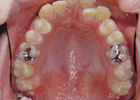

歯を抜かずに治療ができた例

治療後